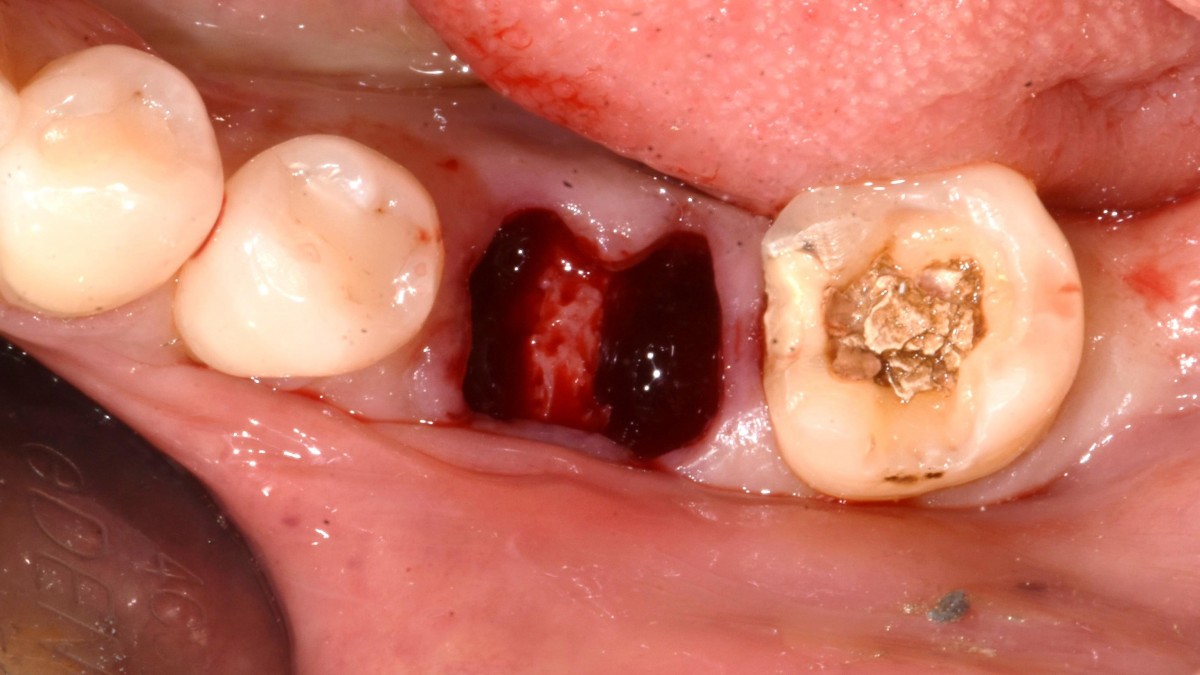

A 51-year-old patient complained of an

old-crowned molar. The lower left molar had a gold crown, and the margin showed discoloration indicative of inner caries. Also, it had furcation-involved periodontitis

with an apical lesion.

Extraction and immediate placement of an implant.